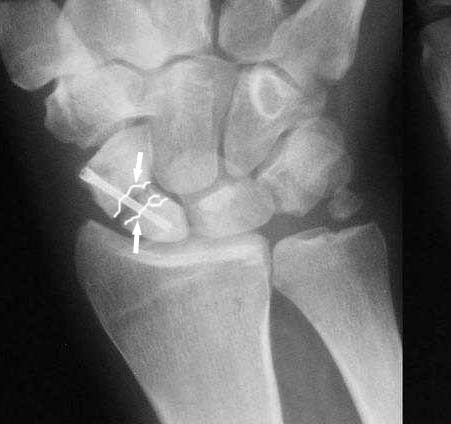

>>Здаётся мне Вы имеете удовольствие видеть ложный сустав ладьевидной кости.

Такое ощущение, что имеющееся состояние ещё не является необратимым (отсутствие склероза отломков на уровне перелома) и обусловлено исключительно нестабильностью (сам винт оказался слабоват или чрезмерные нагрузки привели к срыву фиксации - пациент, заметьте, мотоциклист!)

Почему-то хочется верить, что можно добиться сращения, если вернуть кости стабильность путём компрессионного остеосинтеза более мощным винтом без открытого вмешательства на компрометированной зоне и защитить фиксацию строгим соблюдением режима. Я сильно ошибаюсь?

Ув. Данил! По моему мнению все-таки ложный сустав -склероз отломков (приложение), 5 мес, диастаз. Для подтверждения можно выполнить КТ кистевого сустава (формирование замыкательной пластинки, склероз концов отломков и т.д.,), а так же по КТ можно выявить сохраняется ли подвывих каких-либо костей запястья или нет. При наличии ложного сустава целесообразно будет удалить винт,обработать концы отломков, разрушив замыкательные пластинки и выполнить остеосинтез ладьевидной кости винтом с костной аутопластикой зоны псевдоартроза (либо гидроксиаппатитом...) Гипс 1,5 мес мин. Снимков найти сейчас не получилось. позже дошлю.